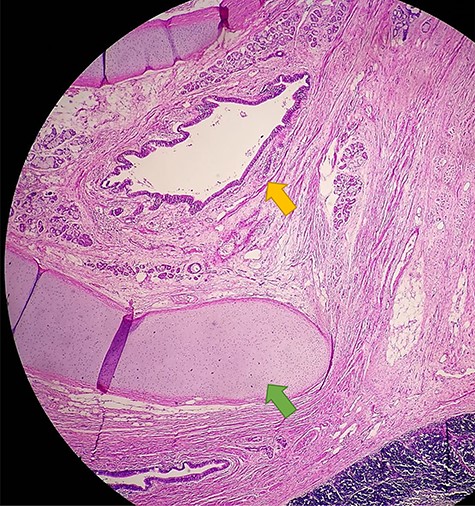

Anatomical pathology test showing the presence of glandular epithelial cells (yellow arrow) concomitant with the presence of cartilage tissue (green arrow)

The patient underwent a total resection of the mediastinal mass via a median sternotomy. Given the extension of the teratoma and adhesions to the chest wall, an additional approach with a left anterior thoracotomy was made (Fig. 2). Entry into the pleural space was performed through the sixth intercostal space to obtain safe visualization of the cavity and proceed to tumor excision. Many adhesions were found to the thoracic wall, diaphragm and phrenic nerve. Additionally, a nutritional artery depending on left internal mammary artery was discovered with collateral veins draining to brachiocephalic vein. A section of the left internal mammary vessels, dissection of the phrenic nerve, ligation of the nutritional vessel, mediastinal tumor excision, ligation of the thymic vessels and thymectomy was performed. Thoracic drainage tubes (two) were placed. The mediastinal tumor, excised in block, was red–gray colored, well circumscribed and capsuled with a size of 15 × 15 × 20 cm. Postoperatively, the collapsed left lung was re-expanded, and the patient was extubated on Day 1 (Fig. 3). The patient recovered from the operation and was discharged on the ninth postoperative day. Preoperative atelectasis of the left lung partially resolved, and the pathological examination revealed a benign mature teratoma with cystic degeneration. Anatomical pathology test showed the presence of glandular epithelial cells concomitant with the presence of cartilage tissue (Fig. 4) The histochemistry test revealed CD3(+) CD20(+) TDT(−) CD5(−) cells. Thymic tissue was negative for malignancy; nine lymph nodes showed reactive follicular hyperplasia.